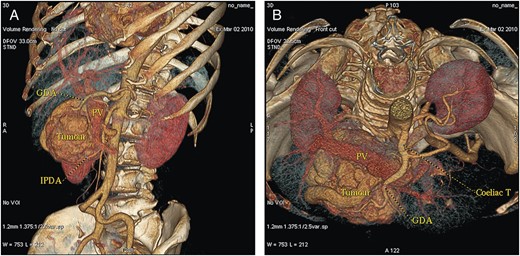

A 53-year-old, obese (body mass index 30.9 kg m−2), Caucasian woman was referred to our department with non-specific abdominal discomfort as the only presenting symptom. A large hypervascularized mass in the area of the pancreatic head was shown on abdominal ultrasonography and computed tomography (CT). There was neither lymphadenopathy nor distant spread found during pre-operative staging. Pre-operative imaging revealed an extremely hypervacularized tumour with abundant collateral vessels from the superior mesenteric artery (SMA), replaced right hepatic artery (HA), gastroduodenal artery (GDA) and right renal artery (RRA), with an early venous filling of the dilated superior mesenteric vein (SMV) and portal vein (PV) (Fig. 1A–C and Fig. 2A and B). The replaced right HA arising from SMA was crossing in between the dilated PV and overfilled tumour-draining veins (Fig. 1B). Abundant venous drainage was found. Extreme dilation of SMV and PV in both extra- and intra-hepatic course could be expected as numerous AV shunts within the tumour were present, but surprisingly, only a non-dilated, gracile splenic vein was found and no spleen enlargement was present (Fig. 1C). For better evaluation of vascular anatomy, selective digital substraction angiography (DSA) was performed. The upper portion of the tumour received main inflow via GDA and replaced right HA, the lower part via several branches of SMA (Fig. 3A and B). Capsular branch of RRA complemented tumour inflow (Fig. 3C).

Cross-sectional CT imaging. (A) Hypervascularized tumour with early venous filling in the arterial phase of CT. (B) Variant subtle right hepatic artery originating from SMA, passing between the dilated PV and draining veins of a paraganglioma. (C) Isolated dilation of the PV with surprisingly gracile splenic vein without any spleen enlargement.